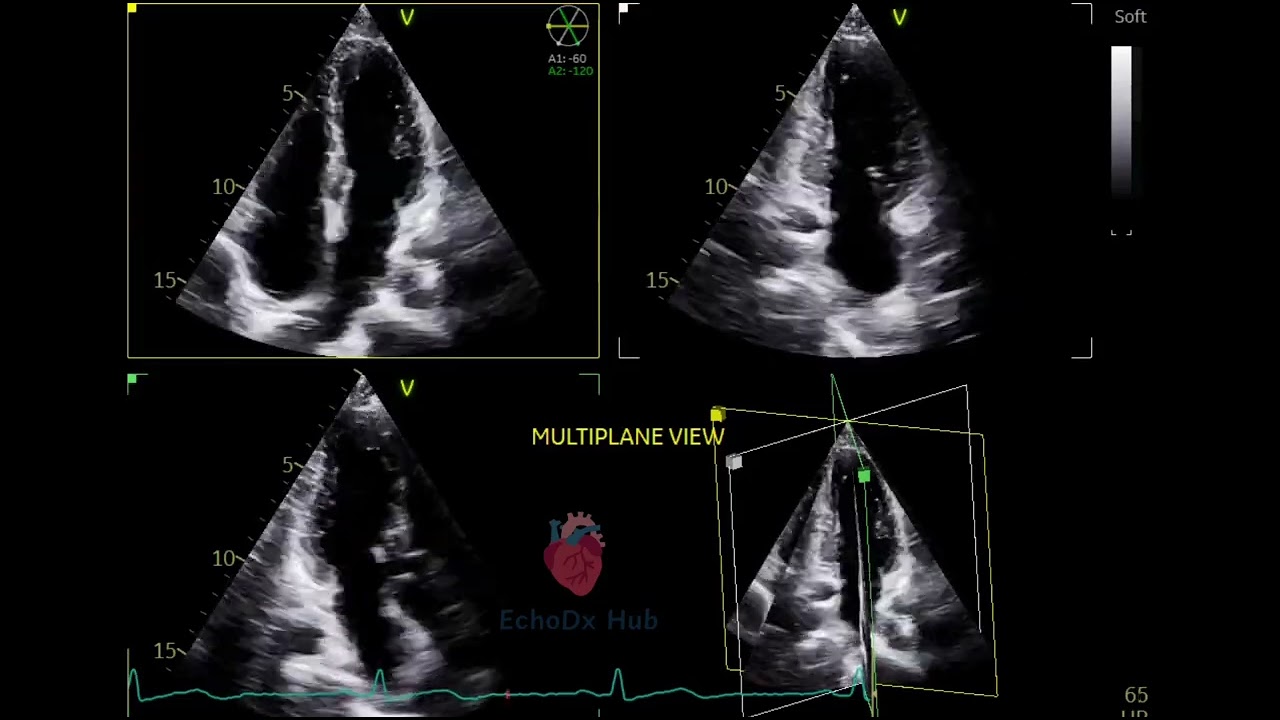

🫀 2D Echo – Apical Multiplane View

The apical multiplane approach involves systematically rotating the imaging plane at the apical window to obtain multiple standard views from a single probe position. This technique enhances anatomical understanding and improves efficiency during echo exams.

🔄 Standard Multiplane Views from Apical Window:

Apical 4-Chamber (A4C) – 0°

LA, RA, LV, RV, mitral & tricuspid valves

Apical 5-Chamber (A5C) – ~10–20° anterior tilt

Adds the LVOT and aortic valve (fifth chamber)

Apical 2-Chamber (A2C) – ~60°

LA, LV, mitral valve (no RV)

Apical 3-Chamber (A3C) – ~120°

LV, LA, aortic valve, LVOT, mitral valve (like PLAX from apex)

📌 Clinical Advantages:

Complete left ventricular assessment (EF, WMA)

Optimal views for Simpson’s biplane calculation

Allows Doppler interrogation of aortic, mitral, and tricuspid valves

Improves detection of apical thrombus, wall motion abnormalities, and valvular pathology

🧭 Probe Technique Tip:

Keep the transducer at the apical impulse point, and rotate the probe (or use electronic rotation on 3D/4D machines) to transition between these views—always ensuring the apex is not foreshortened.

💡 Multiplane imaging = full functional insight

This is a core approach in both 2D and 4D echo, especially for comprehensive ventricular function, valve evaluation, and pre/post-surgical planning.